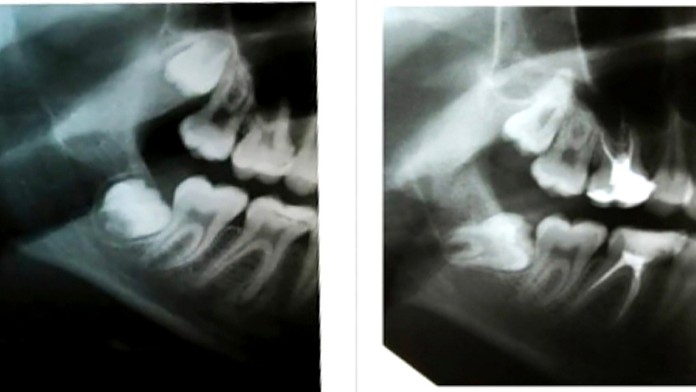

Zuby múdrosti môžu spôsobiť aj rakovinu

Zisťovali sme kedy majú ísť osmičky už naozaj von.

Starostlivosť o takzvané osmičky by sme nemali zanedbávať. Okrem fatálnych prípadov dokážu aj poriadne bolieť. Zisťovali sme kedy majú ísť osmičky už naozaj von, a kedy je návšteva u lekára zbytočná.